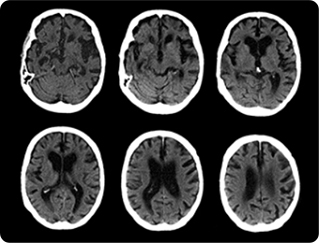

뇌혈관 CT 촬영

뇌혈관 CT는 뇌혈관 질환이 의심되는 환자의 경색과 출혈을 감별하고 뇌종양, 뇌동맥류 등의 뇌질환의 진단, 뇌 수술 후 경과 관찰 등을 위해 시행하는 검사입니다.

빠른 검사 속도를 갖는 다중 채널 고속도 CT를 이용하여, 조영제 주사 후 뇌혈관의 구조와 변화를 살펴보기 위한 검사로 동맥류 같은 혈관이상의 진단을 가능케하며 혈관의 개통성 유무 및 협착 정도를 입체적으로 평가할 수 있습니다. 검사 전 최소 4시간 이상의 금식이 필요하며, 미리 확보한 주삿바늘로 조영제를 주입하며 CT촬영을 하게 됩니다.

뇌혈관 CT 검사대상

평소보다 두통이 잦을 때

어지러움이 느껴질 때

고혈압, 당뇨, 고지혈증 등의 만성질환자

혈관질환이 있으신 분

갑자기 팔다리에 마비가 오거나 구토, 의식장애 등이 발생한 경우

50세 이상의 정기적인 뇌(머리) 검사

뇌혈관 CT 촬영으로 알 수 있는 질환들